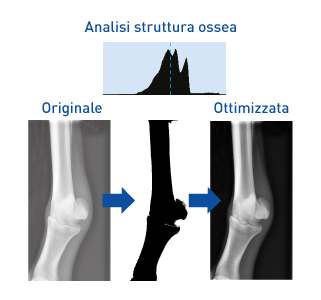

Ottimizzazione automatica

Il software ImagPilot ti permette di passare dallo scatto della radiografia alla diagnosi in pochissimi click! Con ImagePilot, non dovrai più selezionare la taglia dell’animale o la parte anatomica prima di far l’esame! L’algoritmo di ottimizzazione automatica riconosce la parte oggetto di esame ed applica automaticamente i filtri necessari per offrirti sempre l’immagine migliore!